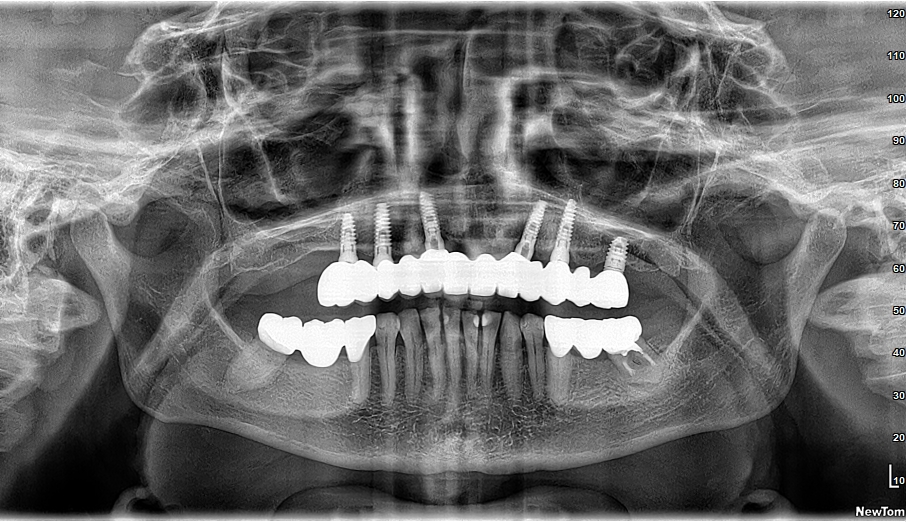

A dental implant is a titanium or zirconium screw placed into the maxillary or mandibular bone through minimally invasive surgery. This screw acts as an artificial root, and a crown, bridge, or denture is placed over it, resulting in an appearance and function similar to a natural tooth.

Before starting treatment, a clinical and radiological assessment is conducted to determine the implant’s viability.